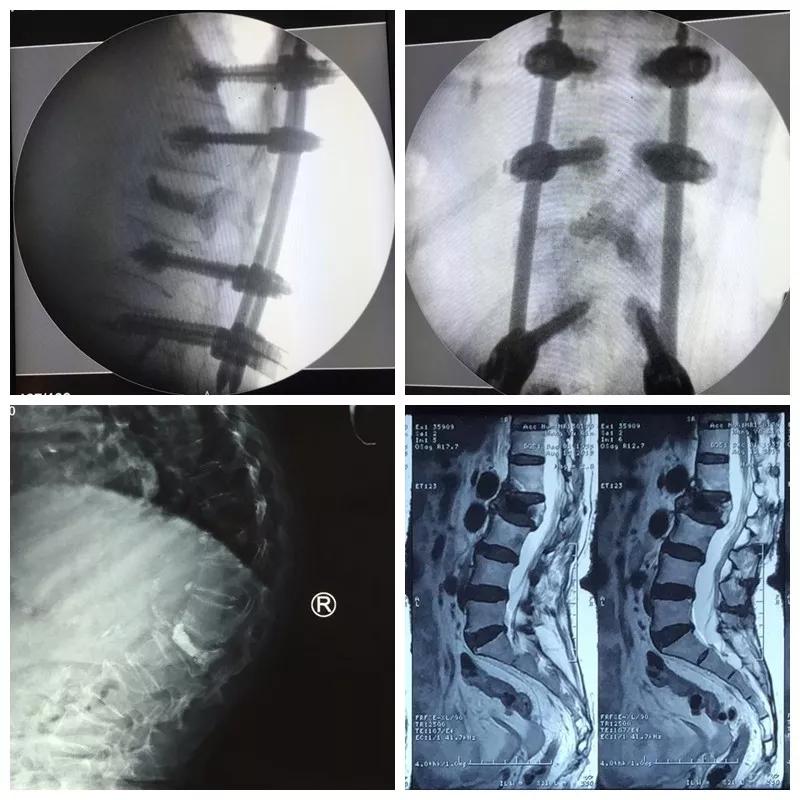

近日,色花堂 骨一科微创团队为一位85岁高龄的患者,运用骨水泥钉道强化技术治疗腰椎骨折后再发后凸畸形,效果满意。

王奶奶今年85岁,1年前摔倒后因骨质疏松导致了腰2椎体压缩骨折,行介入骨水泥治疗,疼痛解除,效果满意。可是后来王奶奶不小心再一次摔倒,驼背明显加重,并又出现了顽固的腰背疼痛和右下肢抽麻,家人把王奶奶送到医院,检查后发现,因为严重的骨质疏松,虽然之前骨水泥加强了骨折椎体,但是没有能阻止骨质疏松的加重,再次摔倒又发生了新的骨折,并且骨折块压住了神经,引起下肢抽麻疼痛。骨一科微创团队经过严谨的术前讨计划与准备,给王奶奶实施了微创手术,一次麻醉同时完成了骨水泥钉道强化矫形、神经减压、新发骨折椎体成形术等三个微创手术,术后驼背畸形纠正、下肢抽麻缓解、腰背骨折疼痛解除,效果理想。老人术后驼背改善了、腰背挺直了,再也不用弯着腰低着头走路了,身高也增加了七八公分,老人开心的说道“我觉得自己又年轻了十几岁”。

郭华院长介绍:骨水泥治疗骨质疏松性压缩骨折已成为常规有效的手术,但是对于严重骨质疏松的患者,单纯骨水泥不能够阻止脊柱后凸畸形的发生,传统椎弓根钉棒系统治疗脊柱骨折矫形效果好,但在严重疏松的骨质里没有足够的把持力,而我们采用的骨水泥强化钉道技术把两者优点结合起来,克服了骨质疏松钉子无把持力的技术难题,而且再加入经皮微创置钉技术,可以完美解决老人的后凸畸形问题。